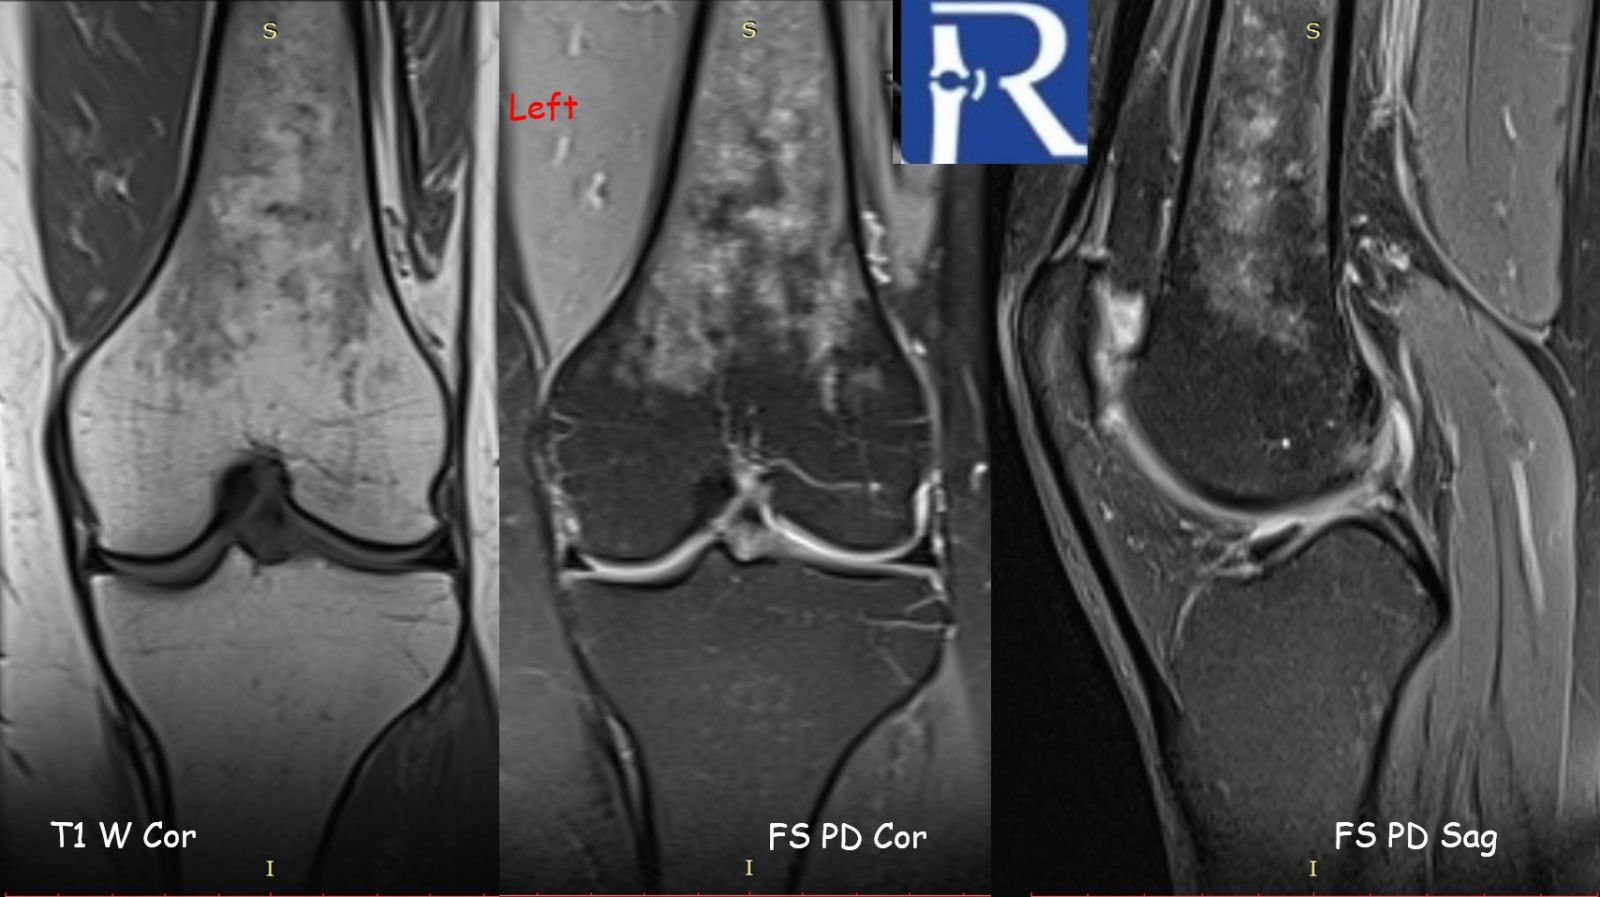

Initial plain radiographs of both knees were unremarkable. However, further evaluation with magnetic resonance imaging (MRI) revealed subcubic lesions infiltrating the bone marrow of both femurs, demonstrated on T1-weighted and fat-suppressed proton density sequences. Given the patient’s prior diagnosis of sarcoidosis, the imaging findings were interpreted as consistent with osseous involvement of the disease.

MRI is the most sensitive imaging modality for detecting skeletal sarcoidosis, particularly for evaluating changes in the bone marrow. However, the imaging appearance is nonspecific and may mimic other pathologies such as metastatic disease, lymphoma, multiple myeloma, or osteomyelitis. Correlation with clinical history and, when necessary, histopathologic confirmation is essential for accurate diagnosis.